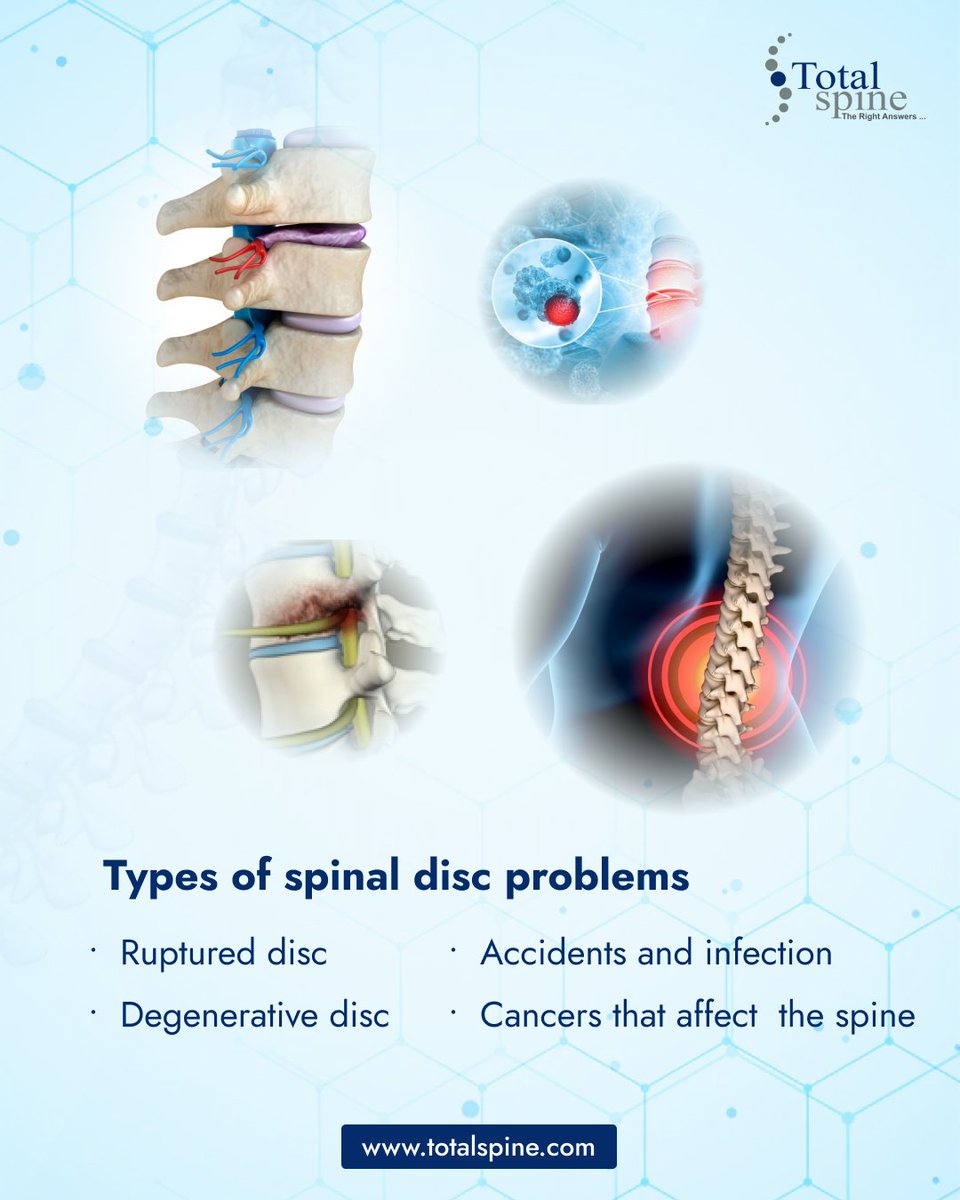

know your disc problems. total spine could help you recover from every kind of disc problems. . . . #spinaldisc #spine #backpain #neckpain #wellness #healthylifestyle #scoliosis #pain #spinehealth #posture #painrelief #doctor #surgery #cancer #orthopedics #kneepain #spinesurgeon